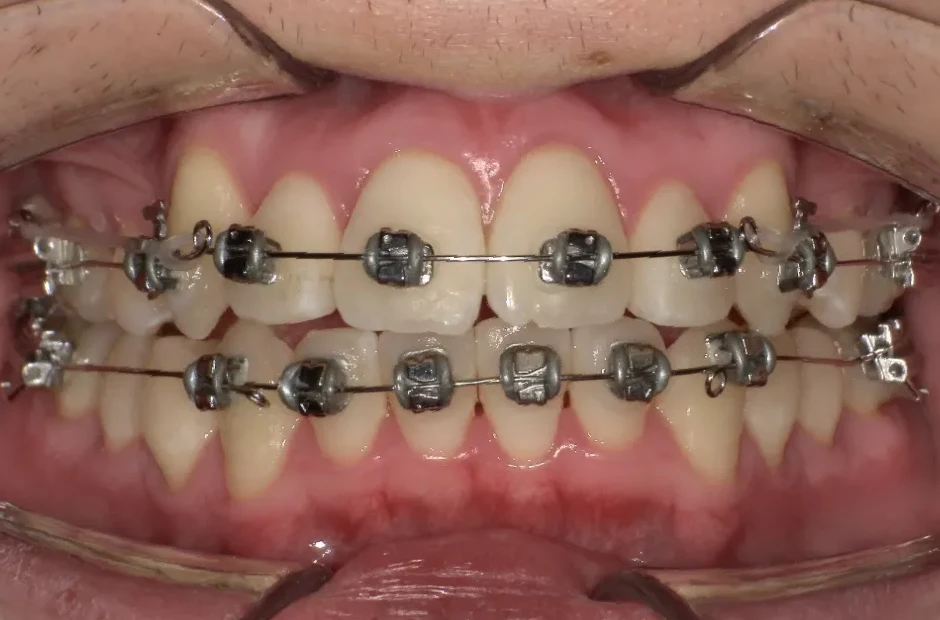

ブラケット矯正

前歯部反対咬合

| 診断名・主訴 | 前歯部反対咬合 |

|---|---|

| 年齢・性別 | 14歳・男性 |

| 治療期間・回数 | 1年2か月 |

| 治療に用いた主な装置 | ブラケット矯正 |

| 抜歯部位 | なし |

| 治療費 | 60万円(税抜) |

| リスク・副作用 | 装置による違和感・疼痛・歯肉退縮・歯根吸収・虫歯のリスクなど |

治療前

治療中